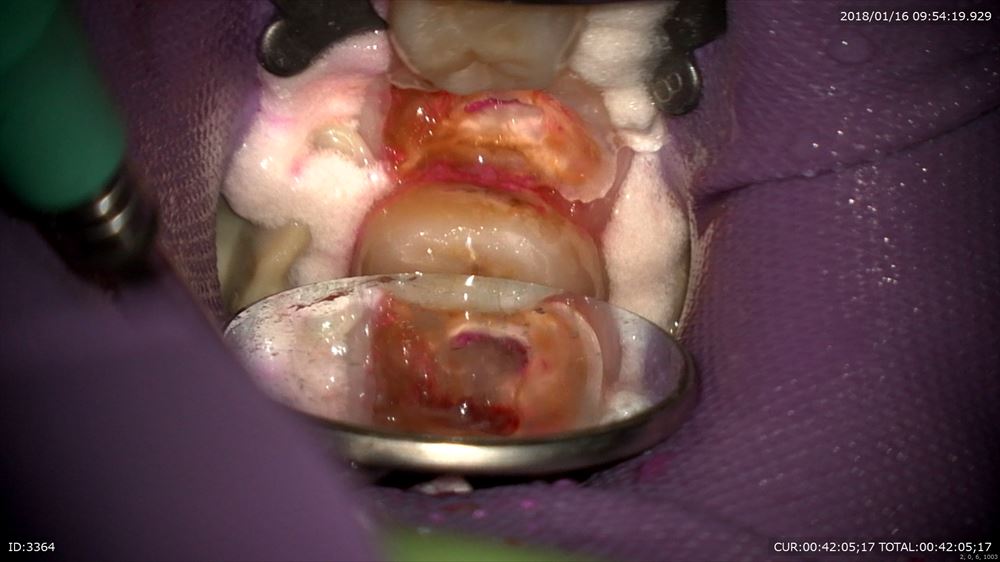

この方はまだ若いのに重度の虫歯を放っておいてこんなになってしまいました。

皆さん虫歯は絶対に放置しないでください。こんな状態になってしまいます。明らかに保存は難しそう。

歯科ドックを行い徹底的に調べました。すると一筋の光が。息肉を丁寧に除去。

イスムスの整理や基本の感染源を徹底的に除去(無痛)

1時間の格闘。4根すべて開通し根管形成まで終了。